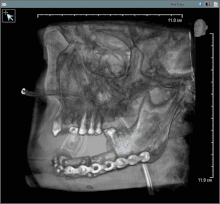

Post-operative image after removal of oral cancer with part of the mandible (feeding tube in nose)

Oral cancer (squamous cell carcinoma) is usually treated with surgery alone, or in combination with adjunctive therapy, including radiation, with or without chemotherapy.[33]: 602  With small lesions (T1), surgery or radiation have similar control rates, so the decision about which to use is based on functional outcome, and complication rates.[33]

Surgery

In most centres, removal of squamous cell carcinoma from the oral cavity and neck is achieved primarily through surgery. This also allows a detailed examination of the tissue for histopathologic characteristics, such as depth, and spread to lymph nodes that might require radiation or chemotherapy. For small lesions (T1–2), access to the oral cavity is through the mouth. When the lesion is larger, involves the bone of the maxilla or mandible, or access is limited due to mouth opening, the upper or lower lip is split, and the cheek pulled back to give greater access to the mouth.[33] When the tumor involves the jaw bone, or when surgery or radiation will cause severe limited mouth opening, part of the bone is also removed with the tumor.